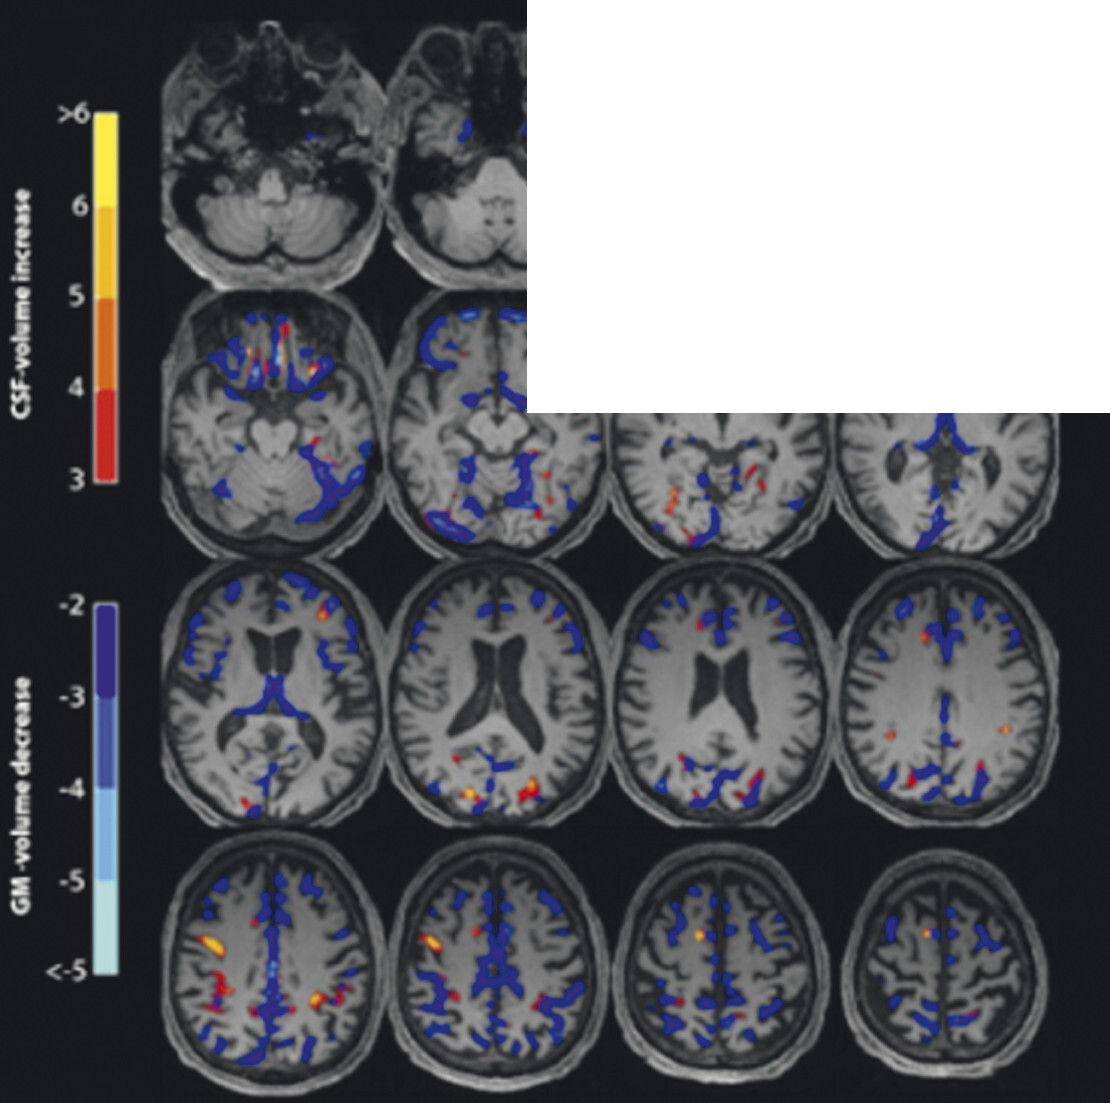

Abb. 69.9 Parkinson-Syndrome: Differenzialdiagnose progressive supranukleäre Parese mit Richardson-Syndrom.

62-jähriger Mann mit über 3 Jahre zunehmender Bewegungsverlangsamung und unsicherem Gangbild. Die MP-RAGE-Aufnahmen zeigen eine deutliche Mittelhirnatrophie mit Kolibri- (a) und Mickey-Mouse-Zeichen (b). Das Mittelhirn/Pons-Verhältnis liegt mit 0,15 im pathologischen Bereich (Normalwert ca. 0,24). Die voxel- und regionenbasierte morphometrische Analyse (c) zeigt neben der Mittelhirnatrophie eine links-frontomesial betonte Atrophie, das FDG-PET (e) einen Hypometabolismus dieser Regionen. Dieses Muster ist typisch für eine sog. Tauopathie und unterstützt daher die Diagnose progressive supranukleäre Parese mit Richardson-Syndrom.

a Sagittale MP-RAGE-MRT-Sequenz.

b Axial reformatierte MP-RAGE-MRT-Sequenz.

c Planimetrische Messungen zur Bestimmung des MR-Parkinson-Index.

d Voxel- und regionenbasierte Analyse.

e FDG-PET. (mit freundlicher Genehmigung von Prof. Dr. Dr. P.T. Meyer, Klinik für Nuklearmedizin Uniklinik Freiburg)